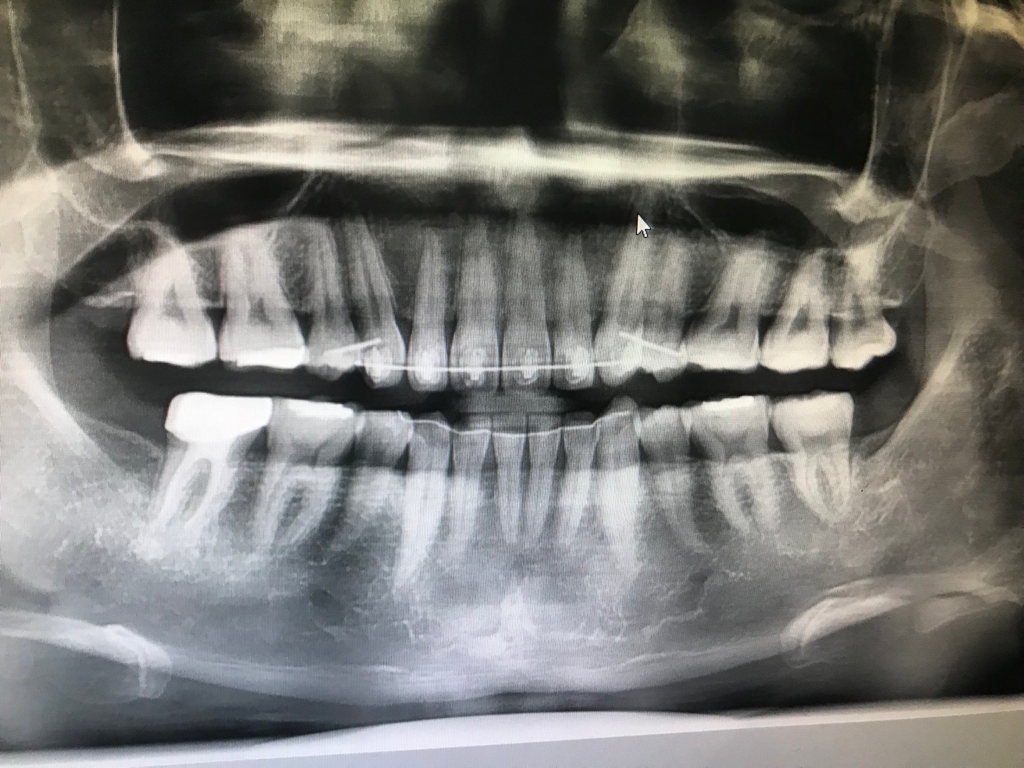

부분교정후 5번치아가 너무 아픕니다

최근 부분 교정을 진행하였는데(상악 1-4까지만 교정기룰 부착한 상태)

두꺼운 철사로 바꾼후 송곳니가 살짝 변화하였는데

(엑스레이 사진상 왼쪽 부분입니다)

송곳니 모서리 부분이 5번치아 옆면 위쪽 부분을 칩니다(4번치아는 예전 발치)

• 1번 째 사진